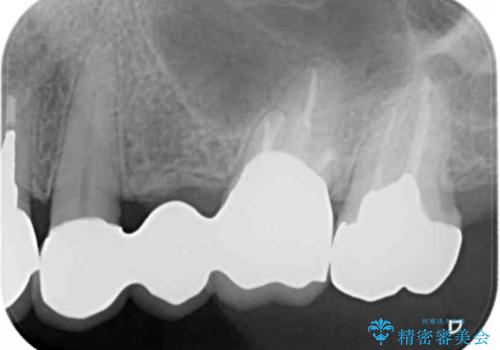

- 長年使用し、見た目の気になってきた金属製のブリッジのやりかえを希望され来院されました。

老朽化した金属製のブリッジを丁寧に除去したのち、金属を用いない審美性の高いセラミック製のブリッジでのやりかえを計画します。